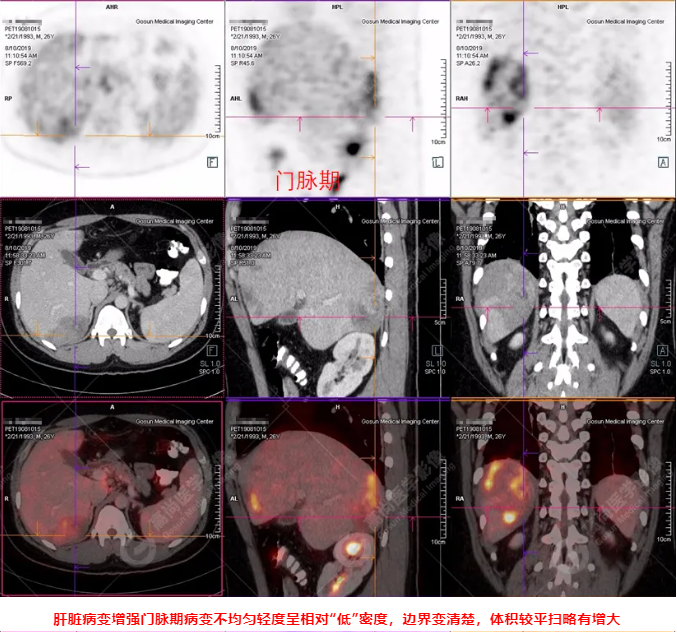

PET/CT全身圖

PET/CT診斷

嗜酸性粒細(xì)胞增多癥肝浸潤(rùn)